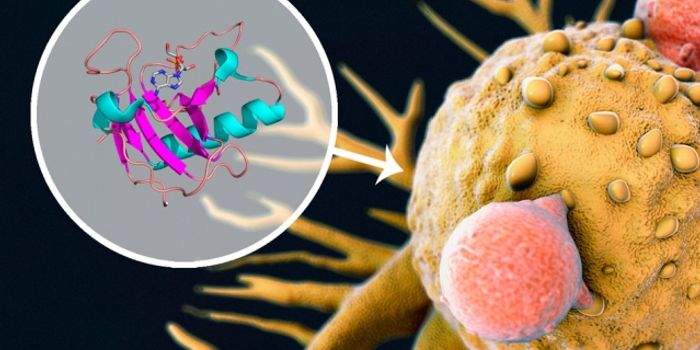

AUG 15, 2017CancerTo creep into distant parts of the body, some cancer cells have developed a knack for shapeshifting – morphing on ...